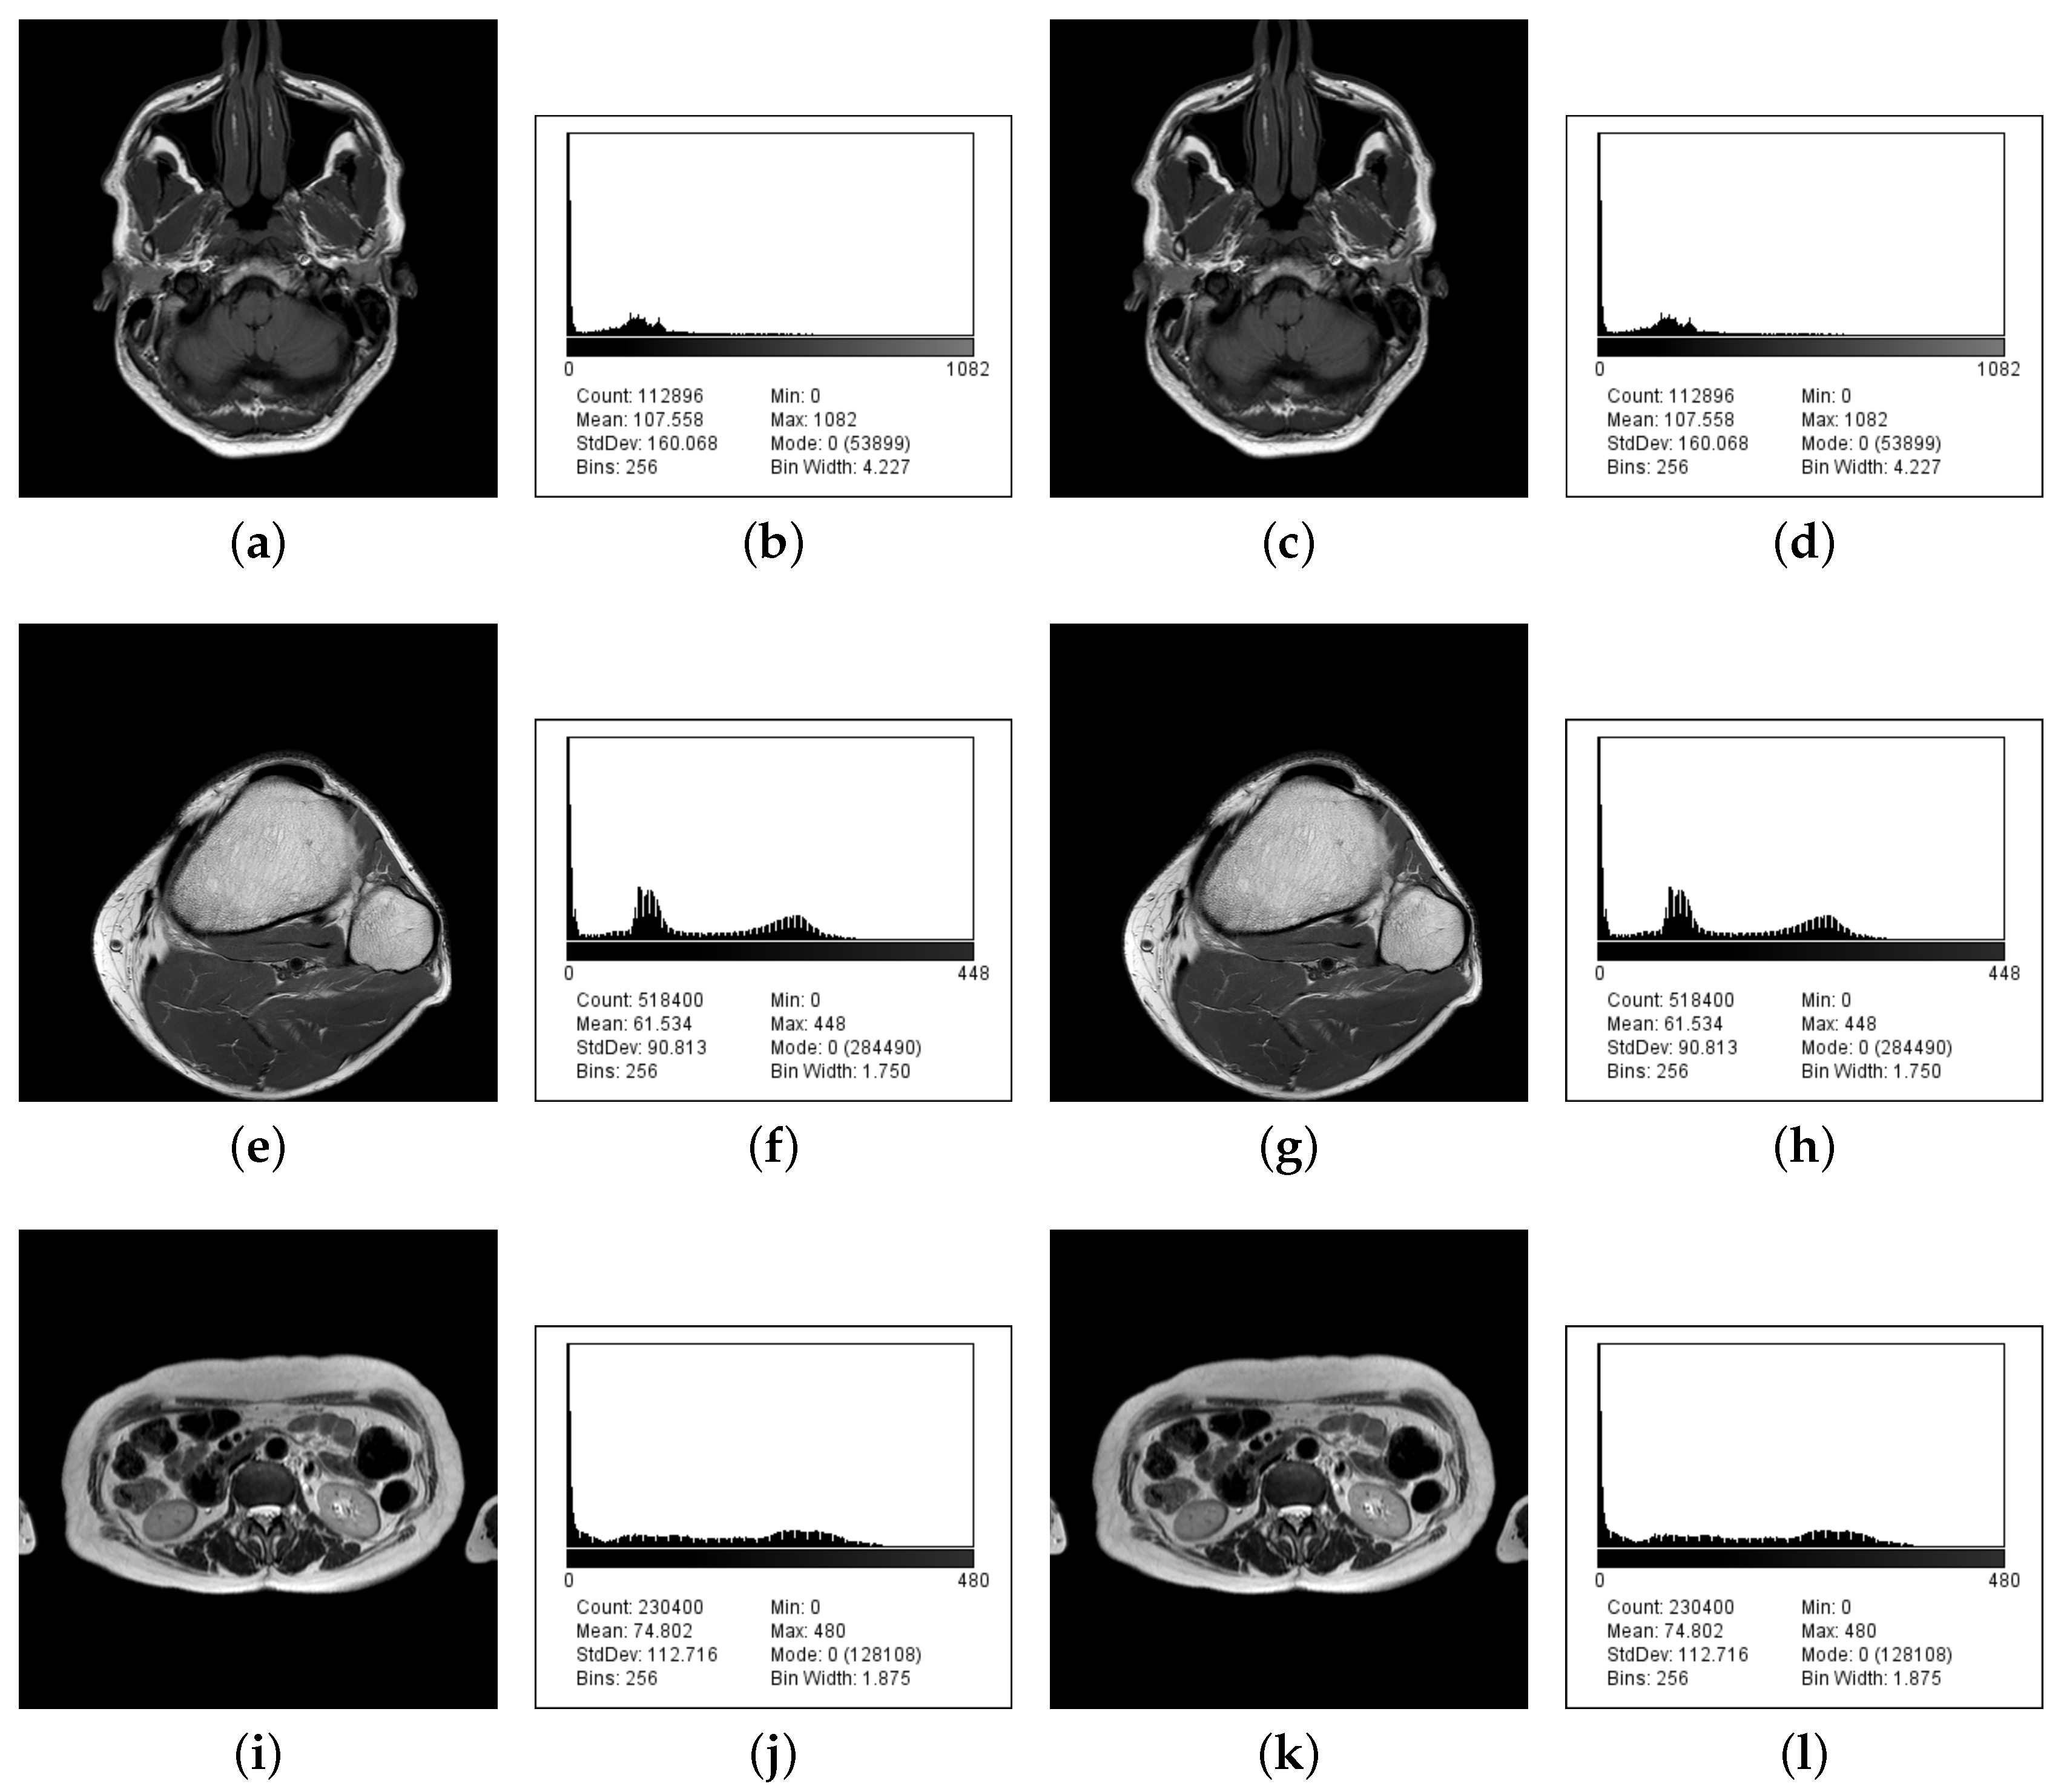

| Input Image | Image Size | Maximum Payload | Percent Volume | Available Levels | Input Levels | Message (Bytes) | MSE | PSNR (dB) |

|---|---|---|---|---|---|---|---|---|

| Brain IM_0001 | 336 × 336 | 83,179 | 73.68 | 1083 | 1050 | 0.0191 | 113.5238 | |

| Brain IM_0002 | 336 × 336 | 83,362 | 73.84 | 851 | 1050 | 0.0192 | 113.4977 | |

| Brain IM_0003 | 336 × 336 | 83,557 | 74.01 | 823 | 1050 | 0.0191 | 113.5218 | |

| Brain IM_0004 | 336 × 336 | 83,341 | 73.82 | 875 | 1050 | 0.0190 | 113.5319 | |

| Brain IM_0005 | 336 × 336 | 83,883 | 74.30 | 834 | 1050 | 0.0191 | 113.5198 | |

| Knee IM_0001 | 720 × 720 | 249,148 | 48.06 | 449 | 1042 | 0.0041 | 120.1618 | |

| Knee IM_0002 | 720 × 720 | 250,531 | 48.33 | 426 | 1042 | 0.0043 | 120.0302 | |

| Knee IM_0003 | 720 × 720 | 251,867 | 48.59 | 461 | 1042 | 0.0043 | 120.0263 | |

| Knee IM_0004 | 720 × 720 | 256,834 | 48.54 | 453 | 1042 | 0.0042 | 120.0637 | |

| Knee IM_0005 | 720 × 720 | 260,969 | 50.34 | 444 | 1042 | 0.0042 | 120.0558 | |

| Liver IM_0001 | 480 × 480 | 109,631 | 47.58 | 481 | 1119 | 0.0098 | 116.4055 | |

| Liver IM_0002 | 480 × 480 | 112,992 | 49.04 | 581 | 1119 | 0.0100 | 116.3465 | |

| Liver IM_0003 | 480 × 480 | 114,107 | 49.53 | 626 | 1119 | 0.0103 | 116.2160 | |

| Liver IM_0004 | 480 × 480 | 115,670 | 50.20 | 643 | 1119 | 0.0098 | 116.4325 | |

| Liver IM_0005 | 480 × 480 | 116,373 | 50.51 | 624 | 1119 | 0.0098 | 116.4383 |